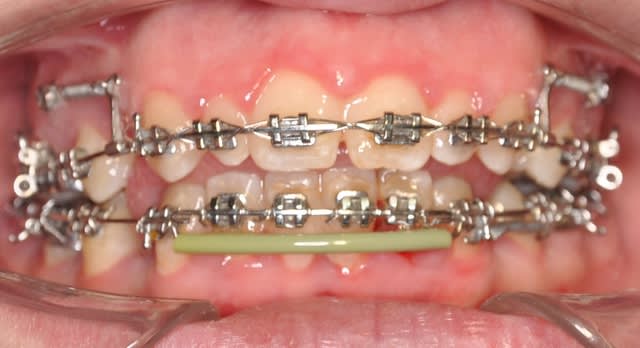

2ème étape

Dsc 0004 lwlouj - Eugenol

Dsc 0003 kobtob - Eugenol

Dsc 0005 pfdneo - Eugenol

Dsc 0006 pndvvp - Eugenol

Dsc 0001 hztqqg - Eugenol

Dsc 0002 b3d098 - Eugenol

Car si je nivèle toute l'arcade à la fois, les incisives inférieures vont se vestibuler avec un bascule horaire du plan d'occlusion, c'est pourquoi j'ai attendue le saut d'articulé pour avoir un cal antérieure pour mes incisives et en plus la lus part des cas je segmente l'arcade sauf si j'ai déjà une linguovertion des incisives inférieures

non,je fait un bay-pass antérieure et je nivèle que les secteurs latéraux au dédut